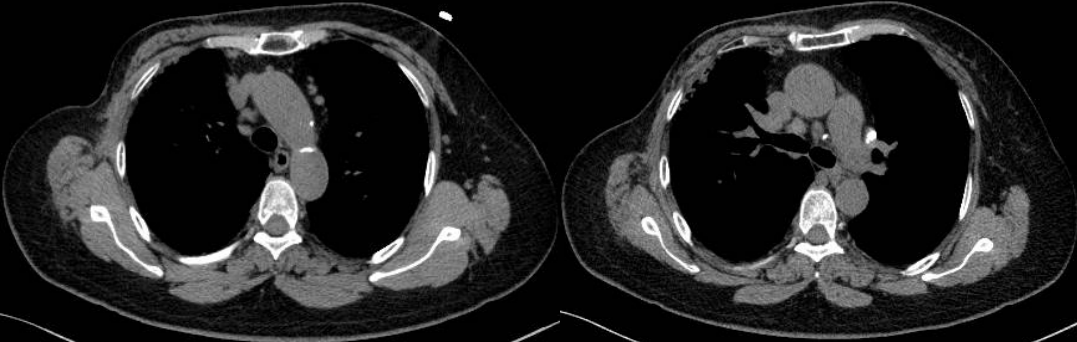

患者8個月后復(fù)查胸部CT示:縱隔、雙肺門淋巴結(jié)較前明顯縮小,較大者約1.4×1.1cm。

此例患者由于乳腺癌的病史,臨床初步懷疑轉(zhuǎn)移。PET/CT顯示縱隔、肺門淋巴結(jié)腫大,且呈對稱性分布,密度均勻,邊界清晰,無明顯融合,F(xiàn)DG高攝?。淮送饪梢姸喟l(fā)腹盆部,頸部淋巴結(jié)次之,分布較散,體積及FDG攝取小于縱隔和肺門淋巴結(jié),也不是乳腺癌術(shù)后易轉(zhuǎn)移的部位。綜上考慮符合結(jié)節(jié)病表現(xiàn),最終得到病理證實,患者因此避免了不必要的抗腫瘤治療。